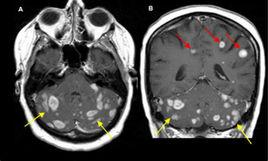

幕上皮髓質交界區多見,常位於頂枕區,多自肺癌、乳腺癌、前列腺癌、胃癌、腎癌和甲狀腺癌等原發灶,經血行轉移而來。常為多發,腫瘤中心常發生出血、壞死、囊變,瘤周水腫明顯。

多發性病灶,周圍明顯水腫,CT上病灶均勻或環形強化,則多可診斷腦轉移瘤,特別是原發腫瘤明確時。多發腦轉移瘤需與多髮結核球、多中心性腦膠質瘤等相鑑別,單發性腦轉移瘤需與囊性星形細胞瘤和囊變淋巴瘤相鑑別。